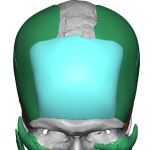

People considering custom jawline implants tend to ask a consistent set of questions. These generally fall into four categories: outcomes, safety, process, and recovery. What are custom jawline implants? Custom jawline implants are patient-specific implants designed from a 3D CT scan of your face. Unlike standard implants, they are digitally created to match your exact Read More…